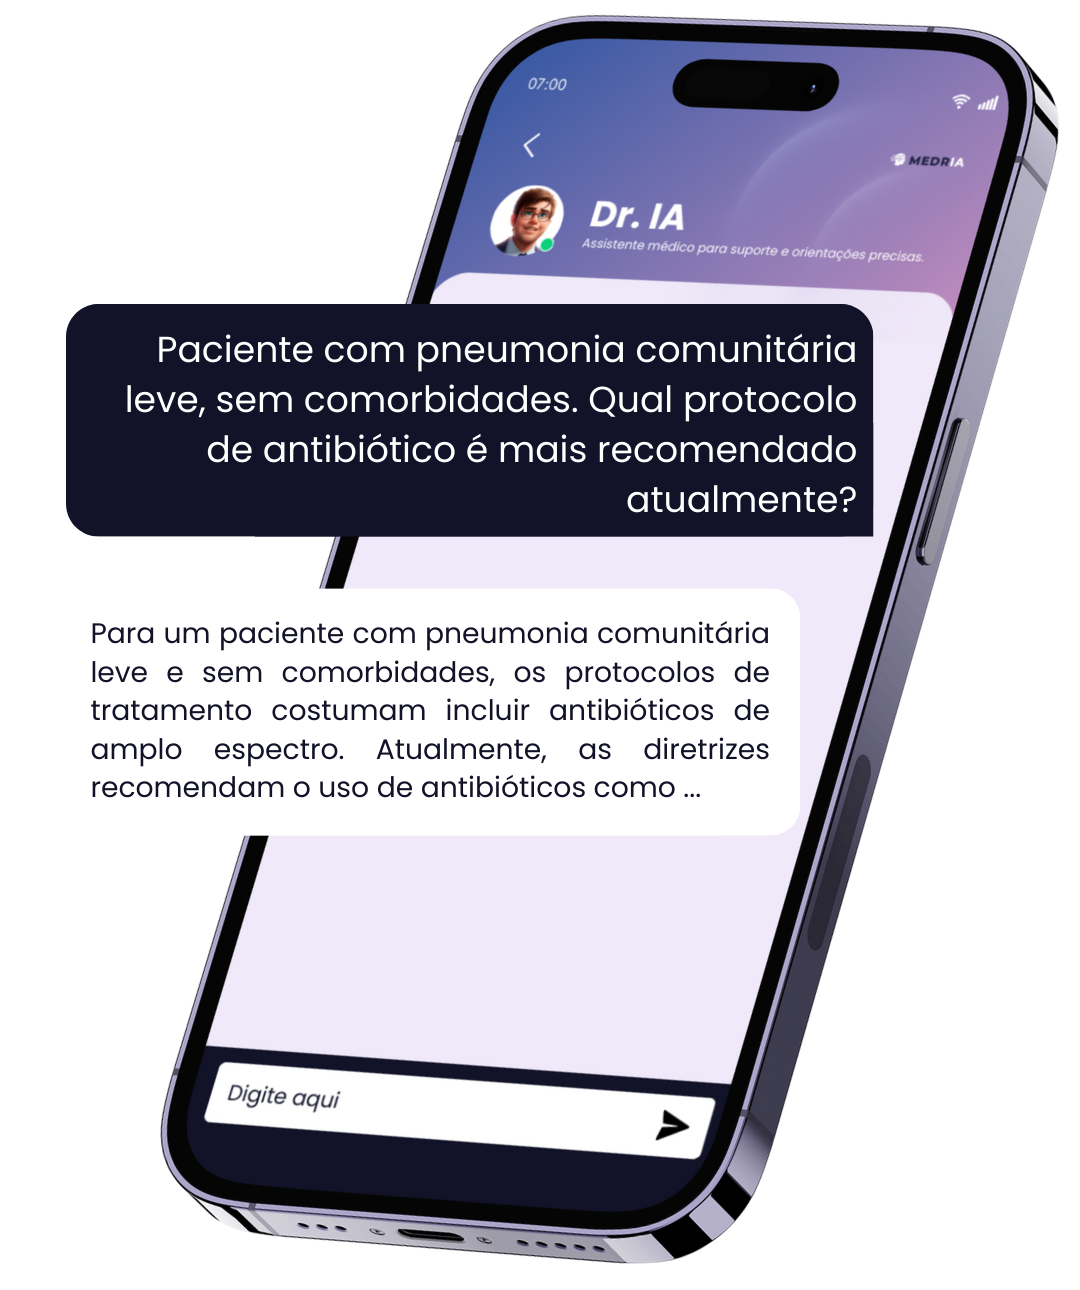

Assistente inteligente

Desenvolvido com base em uma biblioteca médica extensa e atualizada, feita para acompanhar os desafios reais da prática clínica.

Respostas clínicas em segundos, conteúdo técnico e confiável sempre disponível para te apoiar — um parceiro para decisões seguras.